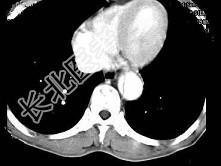

- 单项选择题根据所提供的图像,最可能的诊断是 ( )

A、主动脉瘤

B、主动脉假性动脉瘤

C、主动脉夹层3型

D、主动脉夹2型

E、以上都不是